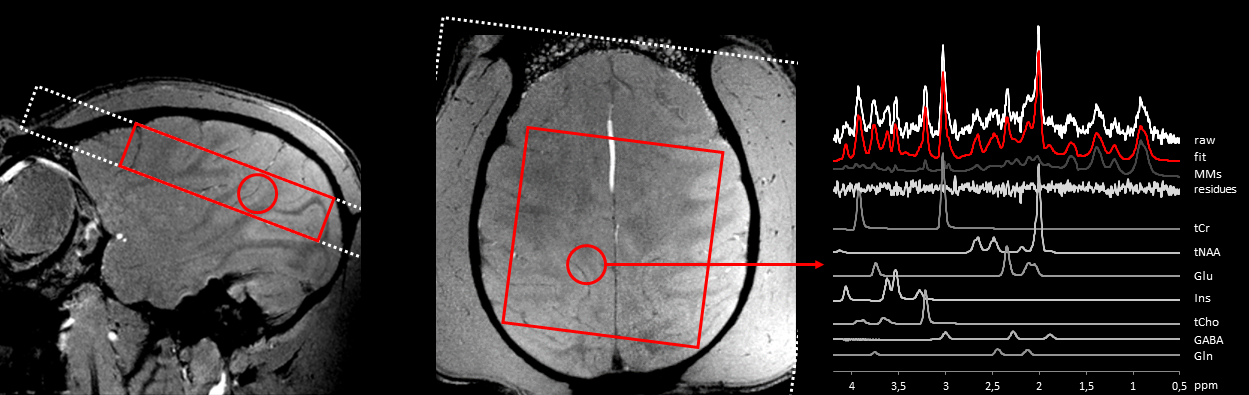

Figure 4 presents the positioning of the MRSI slice and volume-of-interest for one of the monkeys. While the B0 homogeneity achieved across the voxel remained quite modest (FWHM ~80-90Hz), the local homogeneity was sufficient to obtain good quality spectra as shown by the spectral decomposition of one of them.

In vivo 1H MRS data acquired in the macaca rhesus at 11.7 T (2D CSI_STEAM, TE/TM/TR=20/10/1000 ms, sw 4 kHz, 2048 points, NA=12, weighted k-space encoding scheme, in-plane resolution 7.5 x 7.5 mm2, slice thickness 10 mm). On the right panel, a typical spectral decomposition is shown using LCModel 6.2 [3] and a dedicated basis set of model spectra.